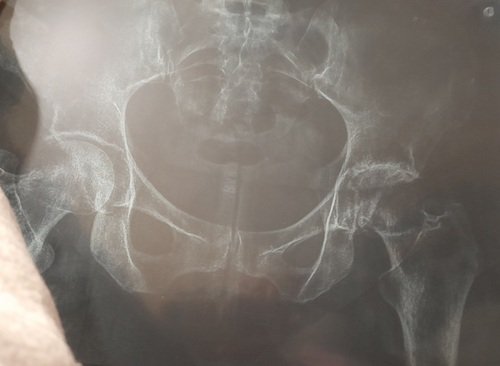

Olá me chamo Aline ,estou passando por uma fase muito difícil pois venho fazendo vários exames e acompanhamento médico.Estou com um problema muito sério de cartilagem que por conta disso terei que realizar uma cirugia no quadril .E devido o valor ser muito alto ,venho caricidamente pedir ajuda de todos que poderem ,pois o valor dessa cirurgia e 85.000,00 .Eu estou na fila do SUS ,só que o retorno e quase impossível pela minha idade, sinto muita dor e por isso não ando sem a muleta ,e fora os remédios fortes que estou tomando devido a dor.Desde de já agradeço a cada um de vocês que Deus abençoe.